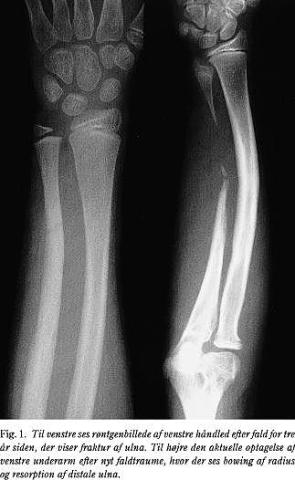

For tre år siden kom patienten i skadestuen efter faldtraume. Der blev konstateret en venstresidig udisloceret ulnafraktur, ca. 10 cm proksimalt for håndleddet (Fig. 1). Der blev anlagt gipsskinne, og patienten blev ikke kontrolleret radiologisk i efterforløbet. Der var angiveligt ikke gener efter frakturen.

Patienten kom på ny i skadestuen efter fald, hvor hun havde taget for sig med ve. hånd. Objektivt fandtes ømhed og mistanke om fraktur af distale antebrachium, men ingen tegn på instabilitet af håndleddet. Røntgenundersøgelse af underarmen viste tiltagende bowing af radius samt resorption af den distale halvdel af ulnadiafysen, men med bevaret distal ulnametafyse. Der var forkortning af ulna og let deformering af den distale radiusepifyse. Der var ingen friske frakturer eller afrivninger (Fig. 1).